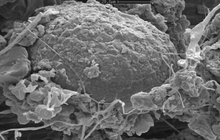

- Examination of cell placement on tissue scaffolds with SEM microscopy